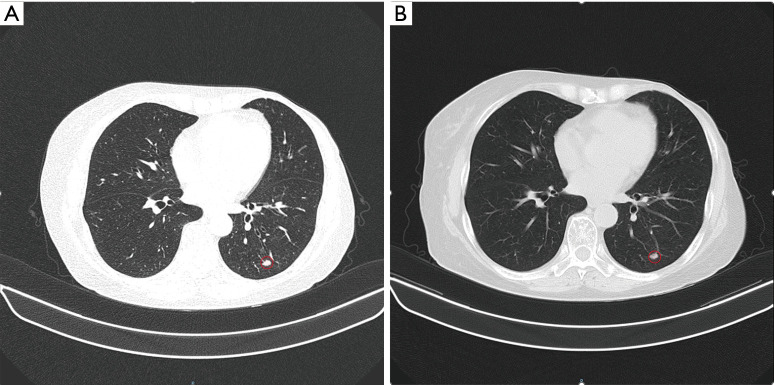

Case description: In this study, we present a case of a 71-year-old woman who was diagnosed with metastatic breast cancer and subsequently developed chronic myeloid leukemia (CML) following her treatment regimen with palbociclib and exemestane. In response to this new diagnosis, the patient commenced therapy with imatinib mesylate while discontinuing palbociclib and receiving exemestane alone for breast cancer. After three months of diligent therapy with imatinib, chronic myeloid leukemia was effectively managed, which permitted the reintroduction of palbociclib at a reduced dosage.